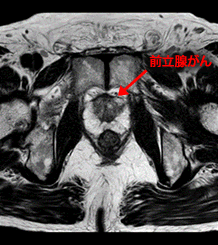

前立腺MRI検査

前立腺がんの疑い症例の局在診断や生検のガイドとしてMRIは有用性を発揮します。

T2強調画像、拡散強調画像、造影T1強調画像を総合的に判断して前立腺内局在診断を行います。

Gleasonスコア:3+4

TNM分類:T2aN0M0

MRI・エコー画像融合生検の結果:

T2強調画像および拡散強調画像陽性部位のみから陽性所見を得た。

T2強調画像

拡散強調画像